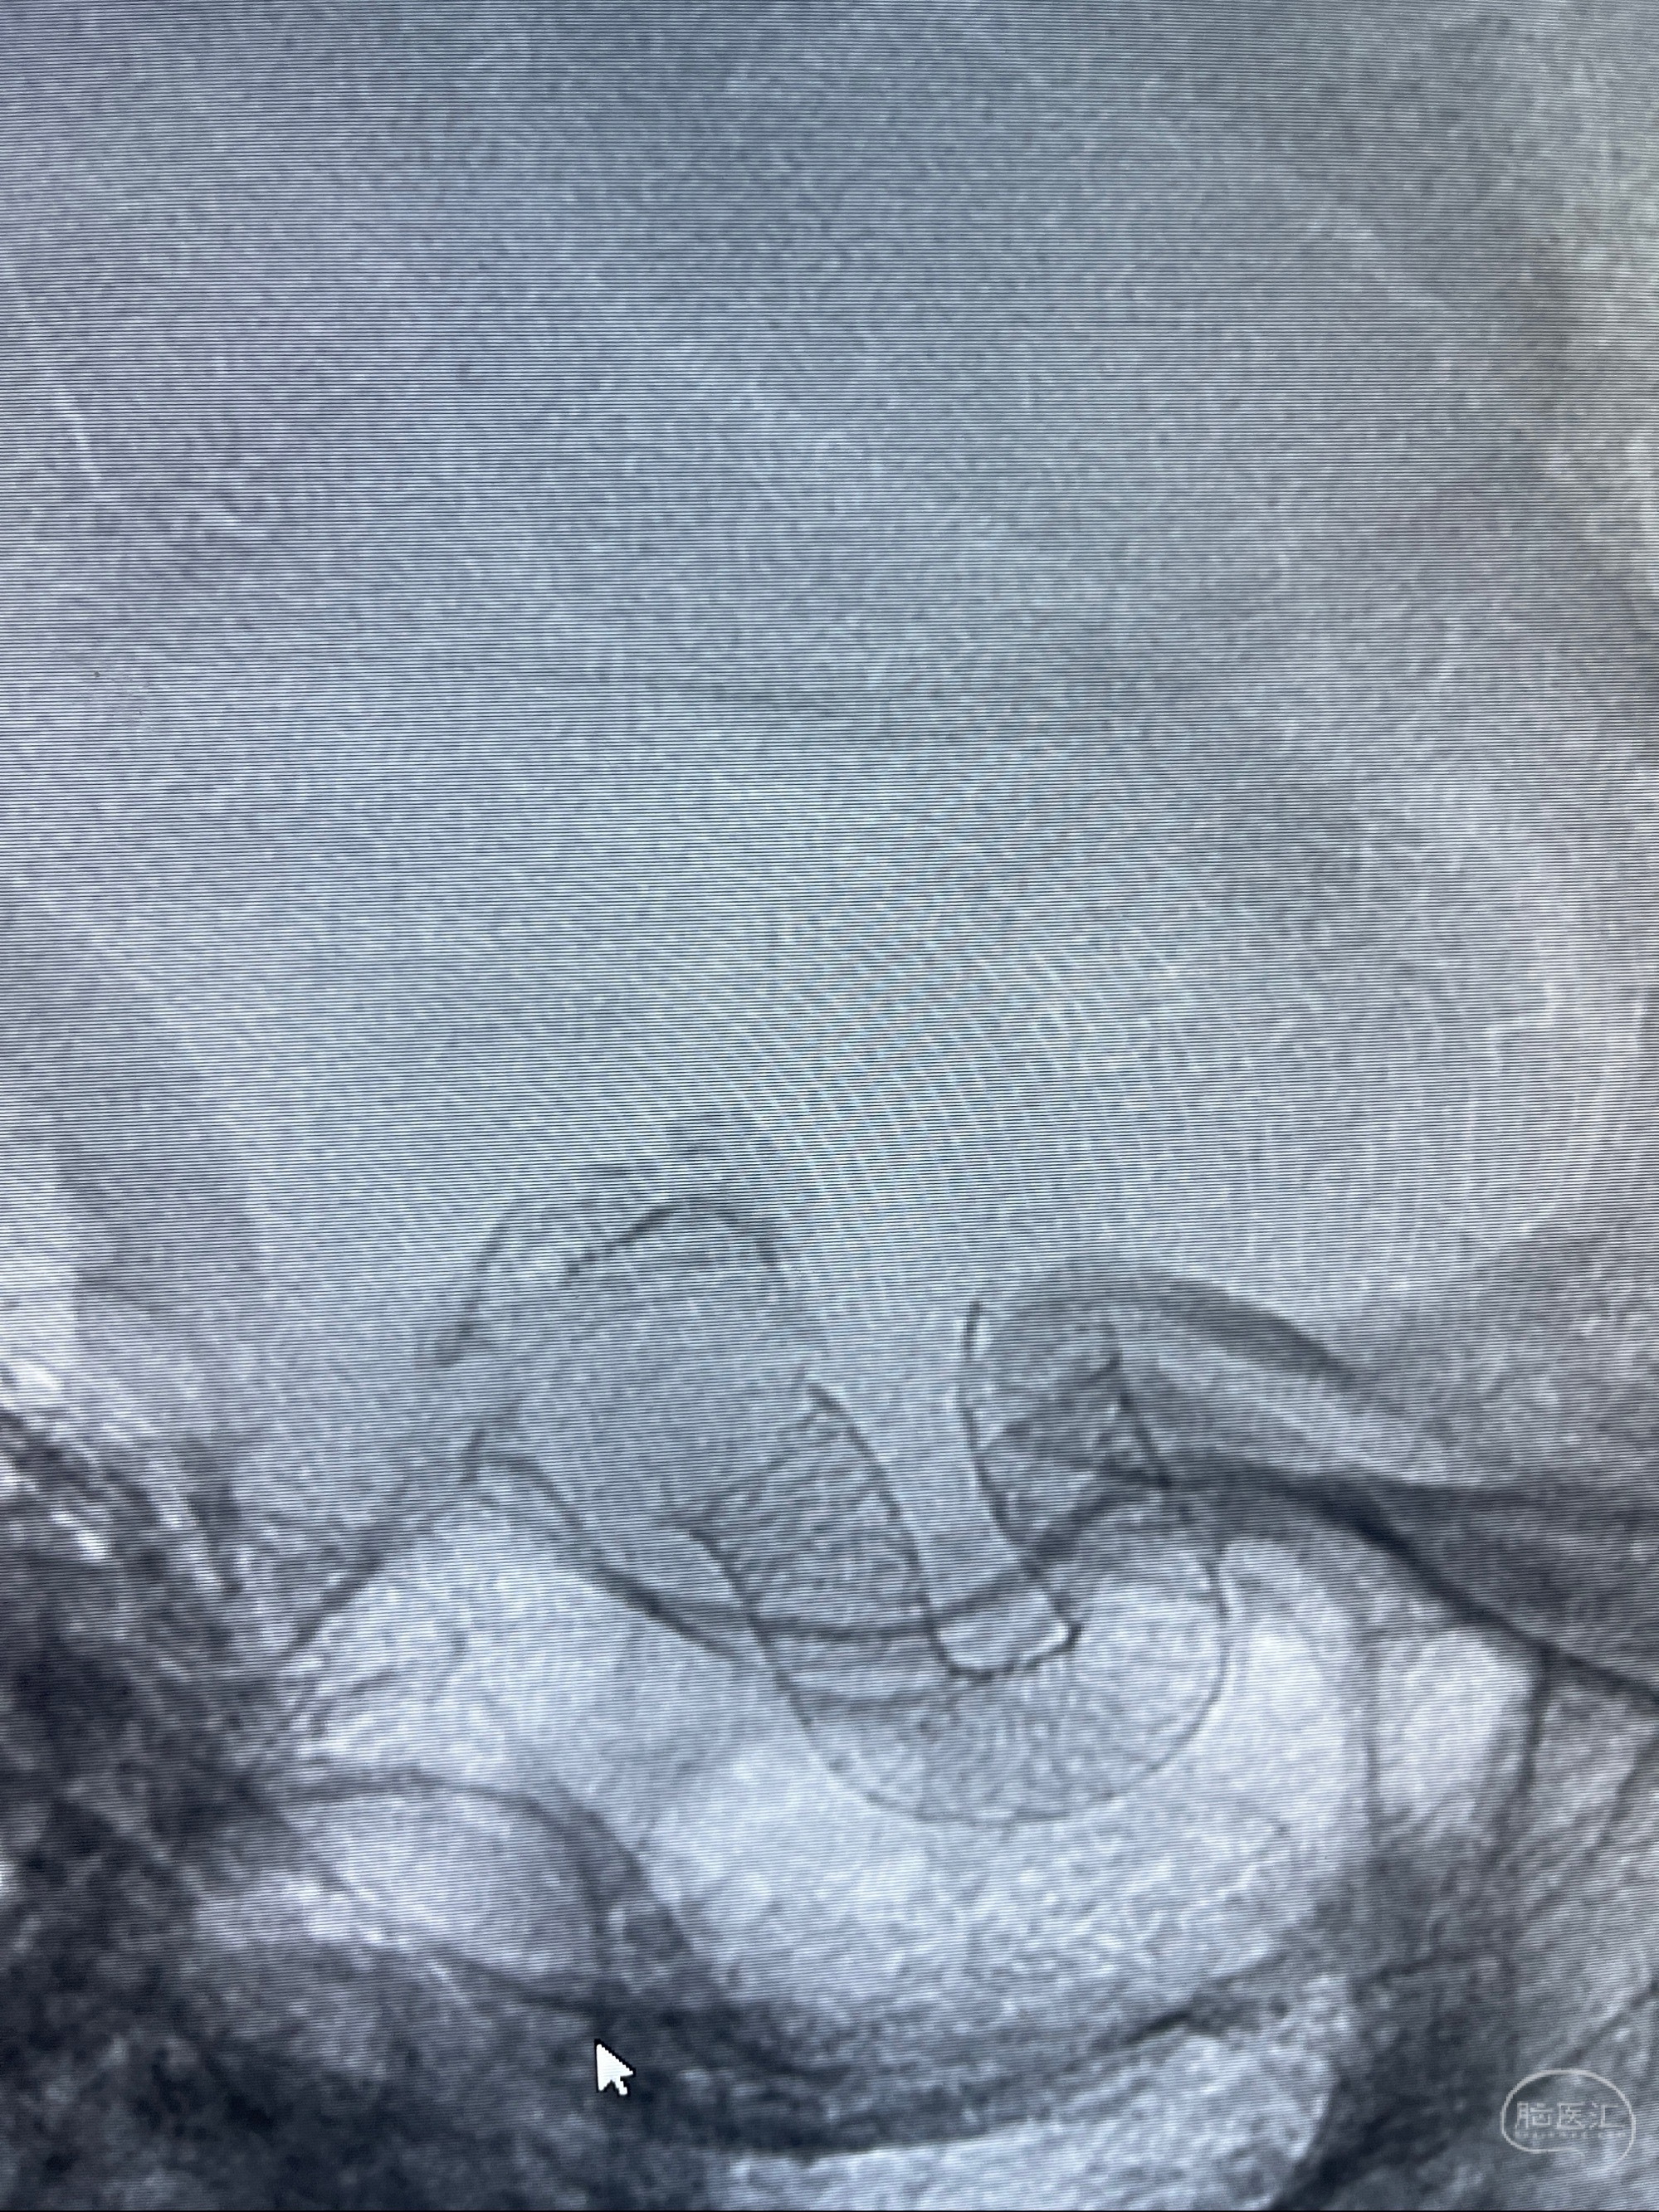

2023-08-01全麻下行双侧颈眼动脉瘤支架辅助栓塞

- pipeling4.5-20mm

- pipeline 4.0-20mm

手术顺利,麻醉苏醒佳,遵嘱动作